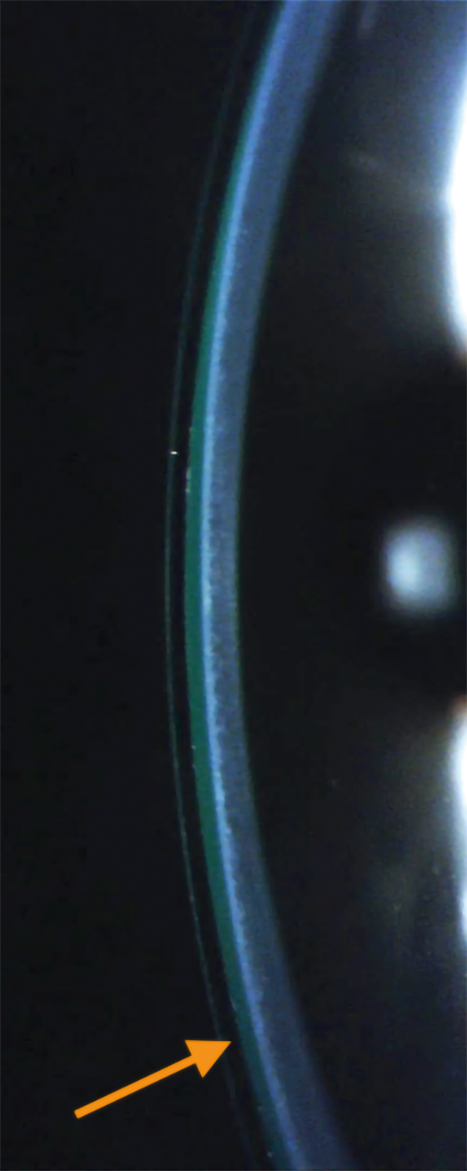

A 63-year-old Caucasian male presented with a chief complaint of blurry vision and “seeing 5 images” with and without spectacles for many years beginning after undergoing Lasik surgery OU that resulted in mild post-Lasik ectasia with OS more affected than OD (Figure 1). The patient’s history included no previous contact lens wear and two traumatic brain injuries due to two separate motor vehicle accidents, which occurred pre-LASIK surgery. Past magnetic resonance imaging (MRI) were reported to be normal. The patient had also been diagnosed with an epiretinal membrane OS result-ing in further mild distortions in vision OS.

The patient’s unaided acuities were 20/30-2 OD, 20/30-1 OS, and 20/30 OU with subjective complaints of shadowing and multiple images in each eye, with OS being more noticeable. The Pentacam corneal topography and pachymetry confirmed irregular astigmatism and showed corneal thickness to be 509 µm OD and 496 µm OS. The pres-ence of a binocular vertical imbalance was noted. Preliminary testing indicated otherwise normal ocular health. Anterior segment biomicroscopy reflected the surgical history with Lasik flaps OU but was otherwise unremarkable.